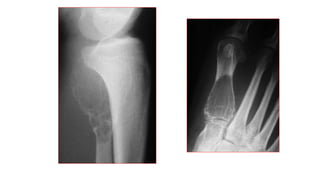

Lesión líticaen metáfisisdel peroné, unilocular,en relacióncon QOS de localización nohabitual

OSTEOSARCOMA NIÑO

11A.: metafisodiafisario

distal femur izq.,

osteolítica irregular con

reacción perióstica

compleja.

OSTEOSARCOMA NIÑO 11A.: metafisodiafisario distalfemur izq., osteolítica irregular con reacción perióstica compleja.